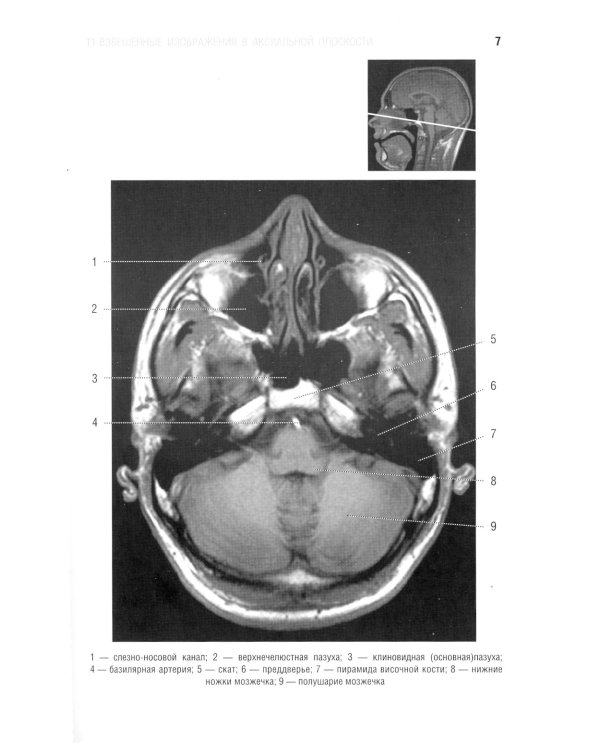

В руководстве представлена нормальная анатомия головного мозга и позвоночника по данным МРТ- и КТ-исследований. MPT-изображения головного мозга отражены в трех взаимно перпендикулярных плоскостях. Отдельная глава посвящена визуализации и нормальной анатомии сосудов головного мозга, в том числе с изображениями, получаемыми при бесконтрастной магнитно-резонансной ангиографии. Для врачей-рентгенологов, специалистов КТ и МРТ, невропатологов, нейрохирургов, а также врачей смежных специальностей. Руководство рекомендовано для обучения студентов медицинских вузов, а также может использоваться в системе последипломного профессионального образования.| Издательство | Элби |